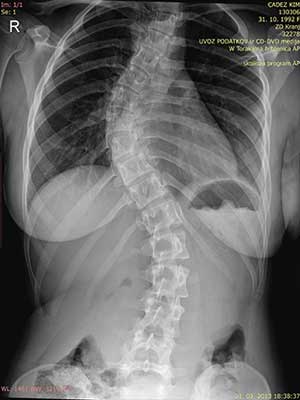

Skolioze lahko zdravimo konzervativno ali operativno. Pomembno je vedeti, da skolioze običajno spontano napredujejo, predvsem ko gre za večje krivine. Ko so skolioze še v začetnem stanju, kar pomeni, da ne presegajo 20° po Cobbu, jih zdravimo konzervativno. Pri konzervativnem…